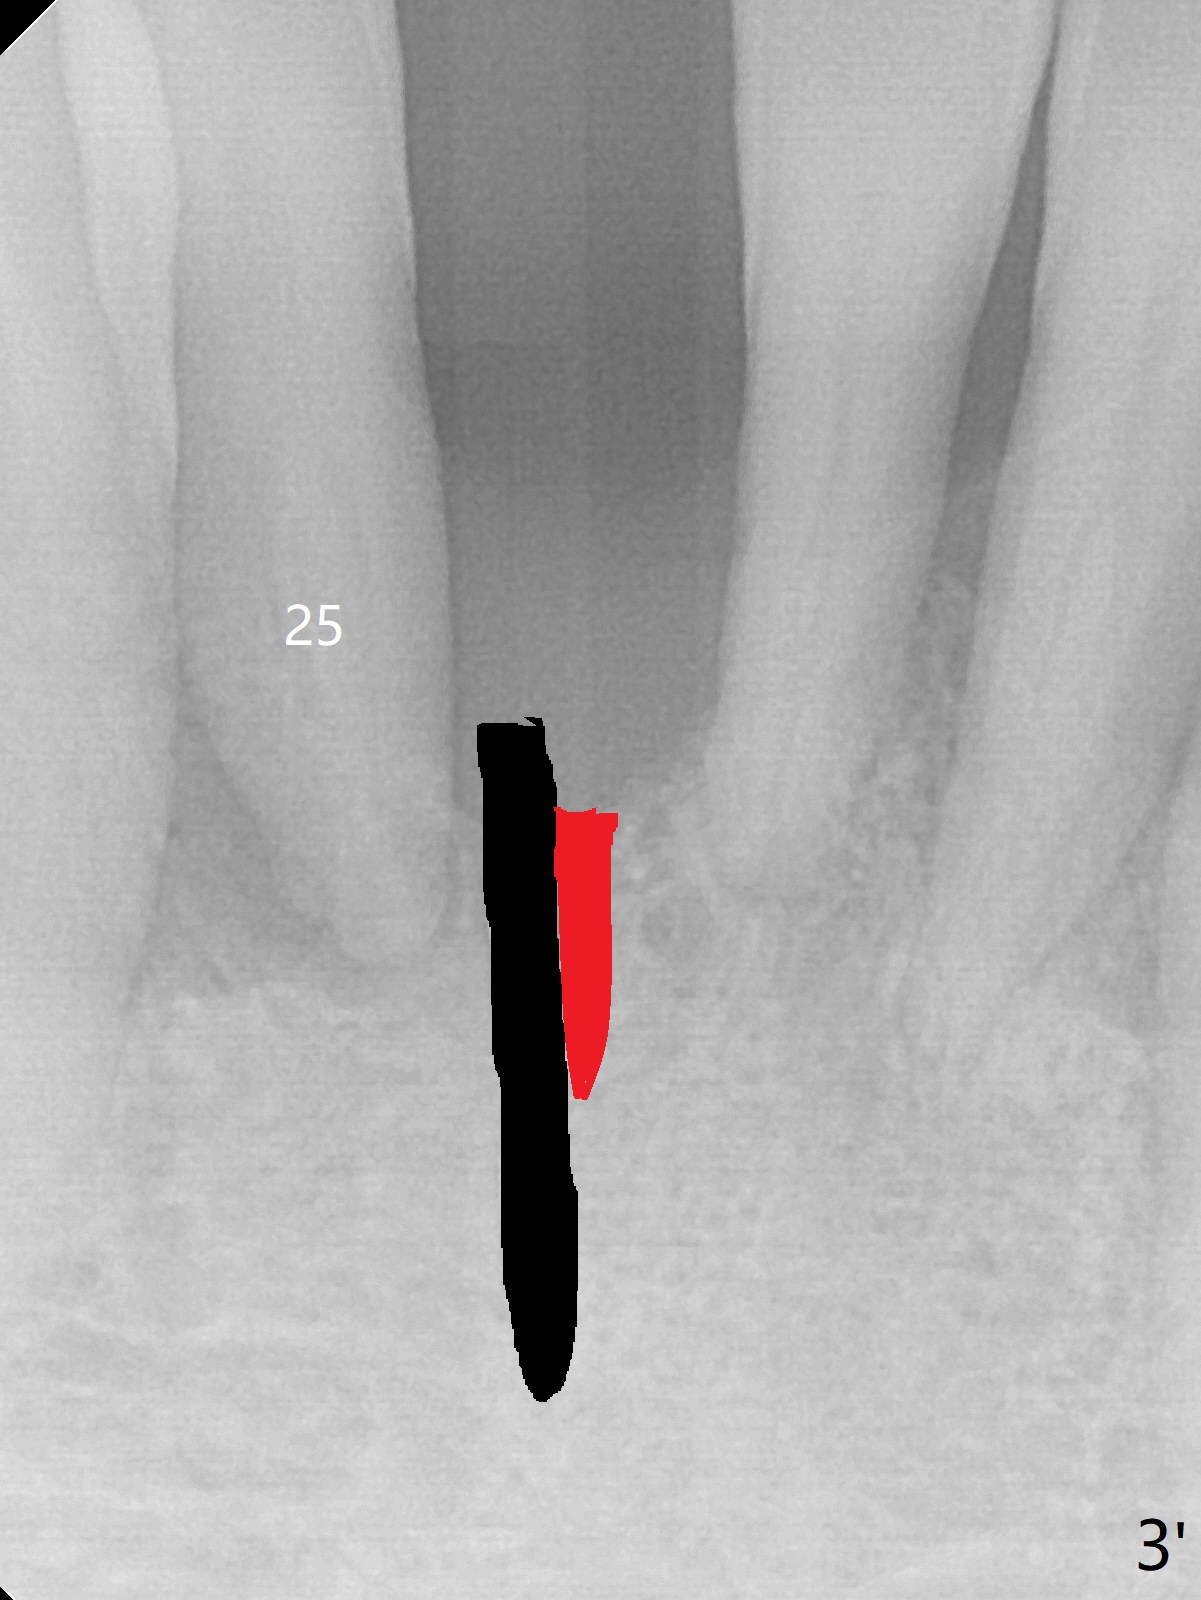

Implant

Out of financial concern, the patient does not agree to have the tooth #26 extracted. Due to atrophy of the most coronal ridge buccally at #25 (Fig.1,2 *), osteotomy is initiated difficult and distal (Fig.3). After 1.2 mm drill removal (Fig.3' black area), Lindamann bur is used to move the osteotomy mesial (red area). A 2x12(4) mm 1-piece implant is placed (Fig.4,5); the buccal defect is packed with allograft (Vanilla, .5-1 mm cancellous/cortical mixture, *). When the tooth #26 fails, a 2 mm implant will be placed (Fig.6 blue). Following abutment adjustment, a provisional is fabricated (Fig.7 P); note the lower incisal edges of #25 and 26, as compared to those of the neighboring teeth. To reduce occlusal trauma, the incisal edge of the tooth #26 has been decreased (Fig.5 open arrow). The implant threads seem not to be exposed 4 months postop (Fig.8), although the tooth #26 has mobility II.